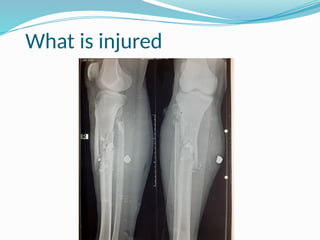

The document discusses the integration of basic sciences with clinical practices in the context of patient diagnosis and management. It emphasizes the importance of understanding anatomy, physiology, pathology, and biochemistry for effective communication and treatment in clinical settings. The speaker, a consultant surgeon, highlights examples like trauma and aortic aneurysms to demonstrate the application of basic sciences in real clinical scenarios.